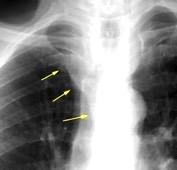

Triada de Garland

Ganglios paratraqueales derechos e hiliares bilaterales

95% de pacientes tienen ganglios hiliares bilaterales aislados o con afectación mediastínica (espec. paratraqueal derecho).

Criado E et al. Pulmonary sarcoidosis: typical and atypical manifestations at high-resolution CT with pathologic correlation. Radiographics. 2010